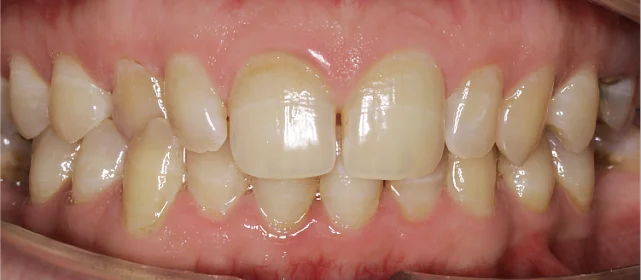

Нарушение соотношения челюстей и неправильное положение зубов — зубные ряды смыкались некорректно, зубы стояли со смещением.

Проблема: В клинику обратилась пациентка — беспокоили неровные зубы и неправильное смыкание. Зубные ряды сходились некорректно, зубы стояли со смещением, что влияло и на внешний вид, и на распределение нагрузки при жевании.

Решение: Поставили элайнеры 3D Smile на обе челюсти. Лечение заняло 4 года и потребовало нескольких последовательных этапов коррекции. Капы менялись каждые 1–2 недели, на контрольных визитах отслеживали прогресс и выдавали новые наборы. Зубы встали в правильное положение, смыкание нормализовалось. Зафиксировали ретейнеры на обе челюсти, изготовили ретенционные капы. Пациентка прошла онлайн-консультацию с ортопедом для оценки дальнейших шагов.